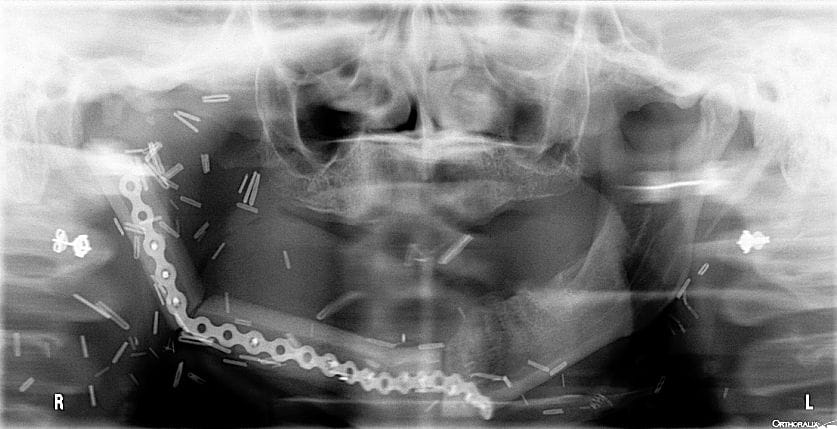

My gut instincts differed from Rob’s, so I showed him a recent panorex image of a patient whose oral cancer lesion took most of her tongue and three-quarters of her jaw. Reconstructive surgery of her jaw was done using her tibia and what looks like a bicycle chain to create a semi-functioning jaw. Tissue grafting was done via the leg tissue, where they harvested her tibia, resulting in two-inch-long leg hair floating inside her mouth at all times. It only took 12 years of smoking to disfigure her by age 35. Note: permission was given by above patient to use her radiographs as an effective way of encouraging smoking cessation.